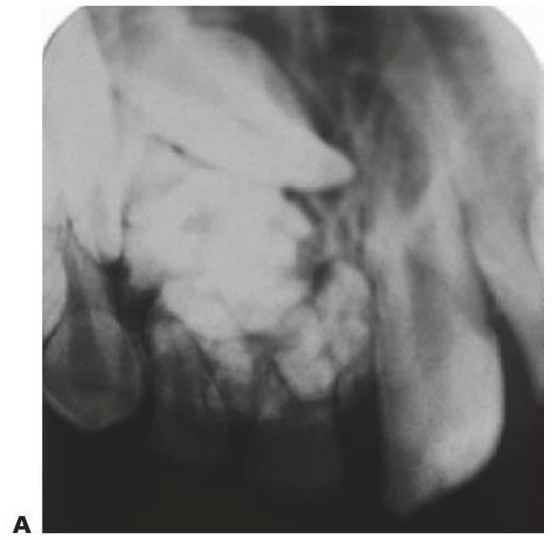

- Resulta esencial localizar la posición del diente que debe extraerse antes de la cirugía. Pueden realizarse radiografías periapicales que emplean la técnica del desplazamiento del tubo (tube-shift) para localizar el diente, pero siempre entrañan la posibilidad de errores e interpretaciones erróneas. De la misma manera, pueden utilizarse radiografías panorámicas y oclusales maxilares estándar. La proyección oclusal de vértice permite obtener una muestra más precisa de la localización horizontal y anteroposterior, por lo que es la preferida (fig. 9.8C) para ayudar a determinar el procedimiento quirúrgico óptimo. Algunos centros prefieren no utilizar esta vía debido a una excesiva radiación en el cráneo.

- Las técnicas digitales de imagen que utilizan tomografías de haz cónico proporcionan una buena definición e imágenes tridimensionales de la cabeza y el cuello y emiten mucha menos radiación que la tomografía computarizada tradicional (TC) (v. fig. 9.18 más adelante).

Los odontomas se producen debido a una alteración de la diferenciación, y suelen presentarse debido a la falta de erupción de un diente permanente. En los odontomas compuestos se encuentran masas de dentículos irregulares en un estroma de tejido blando circunscrito. Los odontomas complejos son alteraciones de tipo desorganizado, con una masa aislada e incidental de tejido calcificado que contiene todos los elementos dentales. Un diente de la serie normal puede sustituirse por un complemento dental normal o bien por un odontoma (fig. 9.12).

Odontodisplasia regional

Se trata de un defecto esporádico en la formación dental con afectación segmentaria que se localiza en general en una parte de un cuadrante, pero que puede cruzar la línea media para afectar al incisivo central contralateral. Esta rara displasia afecta a todos los tejidos dentales y se presenta con dientes hipoplásicos que erupcionan lentamente y que muestran un aspecto radiográfico de diente fantasma. Su etiología no está clara (fig. 9.13).